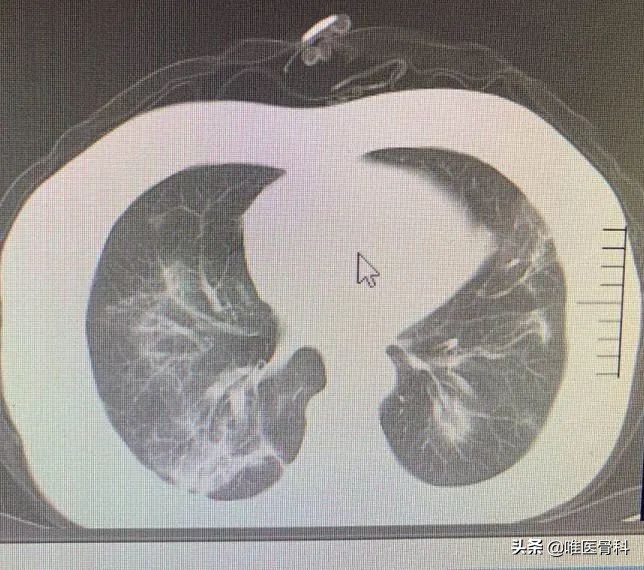

父母回到家中,我阅读了母亲的胸部CT片,尽管我不是呼吸科医生,但是对于如此明显的肺部感染变化,不可能没有判断。

母亲这辈子就没有感染过肺炎,在这种时候感染,加上症状不典型,发热类型属于低热,新冠肺炎感染的可能性极大。我把片子用手机拍下来,发给医疗队的朋友,朋友也验证了我的猜测并且很快给予了我治疗意见。

母亲的肺部CT,磨玻璃样影非常典型